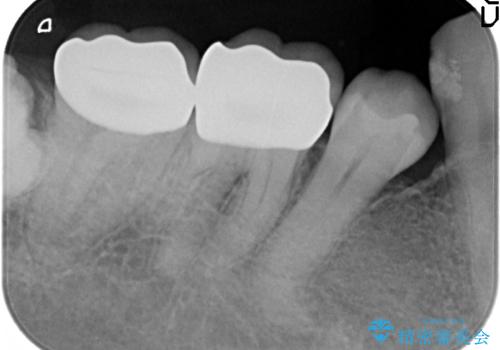

- 昔治療した奥歯の見た目が気になるのでセラミックでやり直したいといらっしゃった方の症例です。

右下6、7の古い詰め物および虫歯を除去後、オールセラミッククラウンによる補綴を行いました。

今回用いたオールセラミッククラウンはジルコニアフレームという白い素材の上にセラミックを盛っているため、審美性が非常に高いのが特徴です。

また、ジルコニアは人工ダイヤモンドの材料にも使われているほど高い強度を持っており、そのためオールセラミッククラウンは審美性だけでなく、奥歯やブリッジの補綴も可能とするクラウンです。